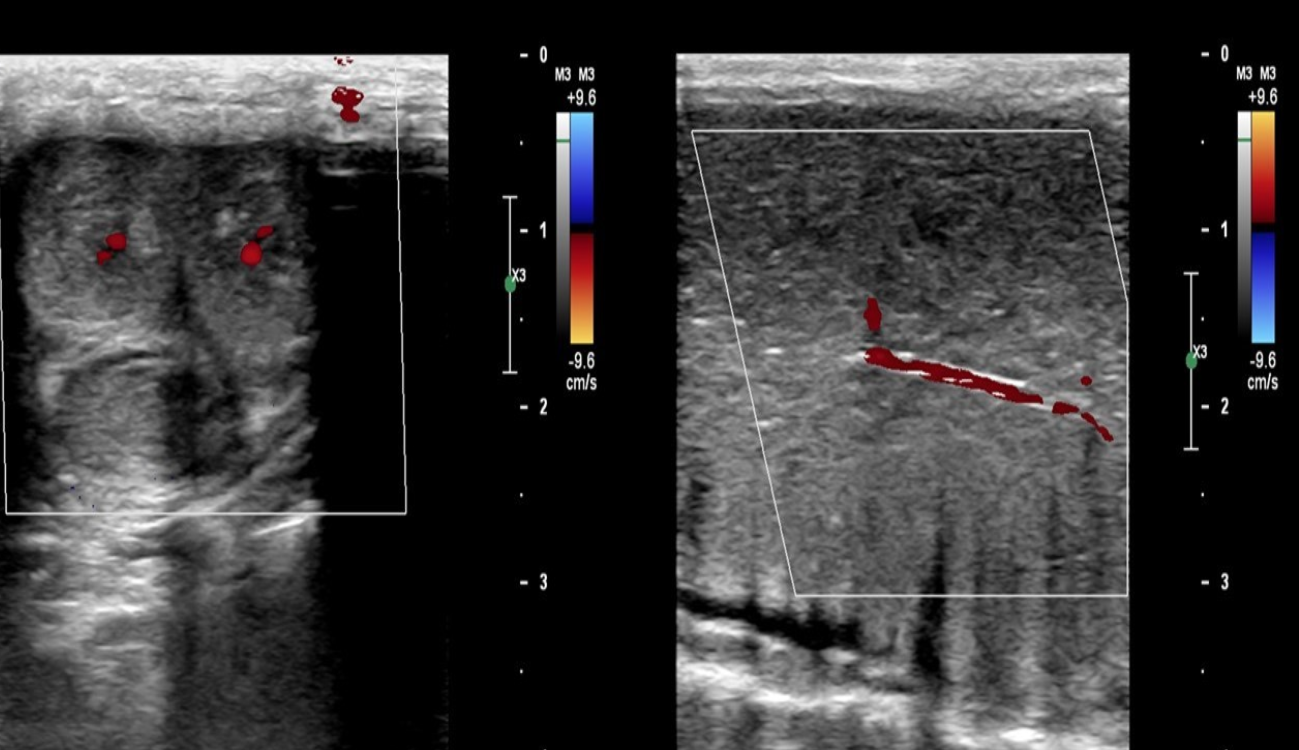

Identify this image.

Cavernosal arteries

What is the normal sonographic appearance for a penile Doppler?

Cavernosal artery PSV > 30 cm/sec

Cavernosal artery EDV < 1 cm/sec

Cavernosal artery diameter increases by at least 75%

Cavernosal artery RI > 0.99

Clinical response to Papaverine injection is greater than 90 degrees